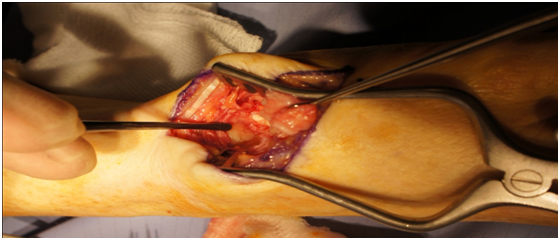

At surgery, the embolisation coils were visible and the pseudoaneurysm had resolved and flattened into a scarred vessel. This was carefully dissected and mobilised, but not excised, to allow the trapeziectomy to be done safely. In addition to the radiographic Grade 2 OA and arthroscopic findings of bare bone, there were signs of loss of cartilage over the scapho-trapezio-trapezoid (STT) articulation (Figure 6); hence a sliver of the proximal trapezoid was also excised.

Figure 6 Intraoperative photograph demonstrating the Scapho-trapezoid joint with previously unknown arthritis (indicated with instrument on the left).